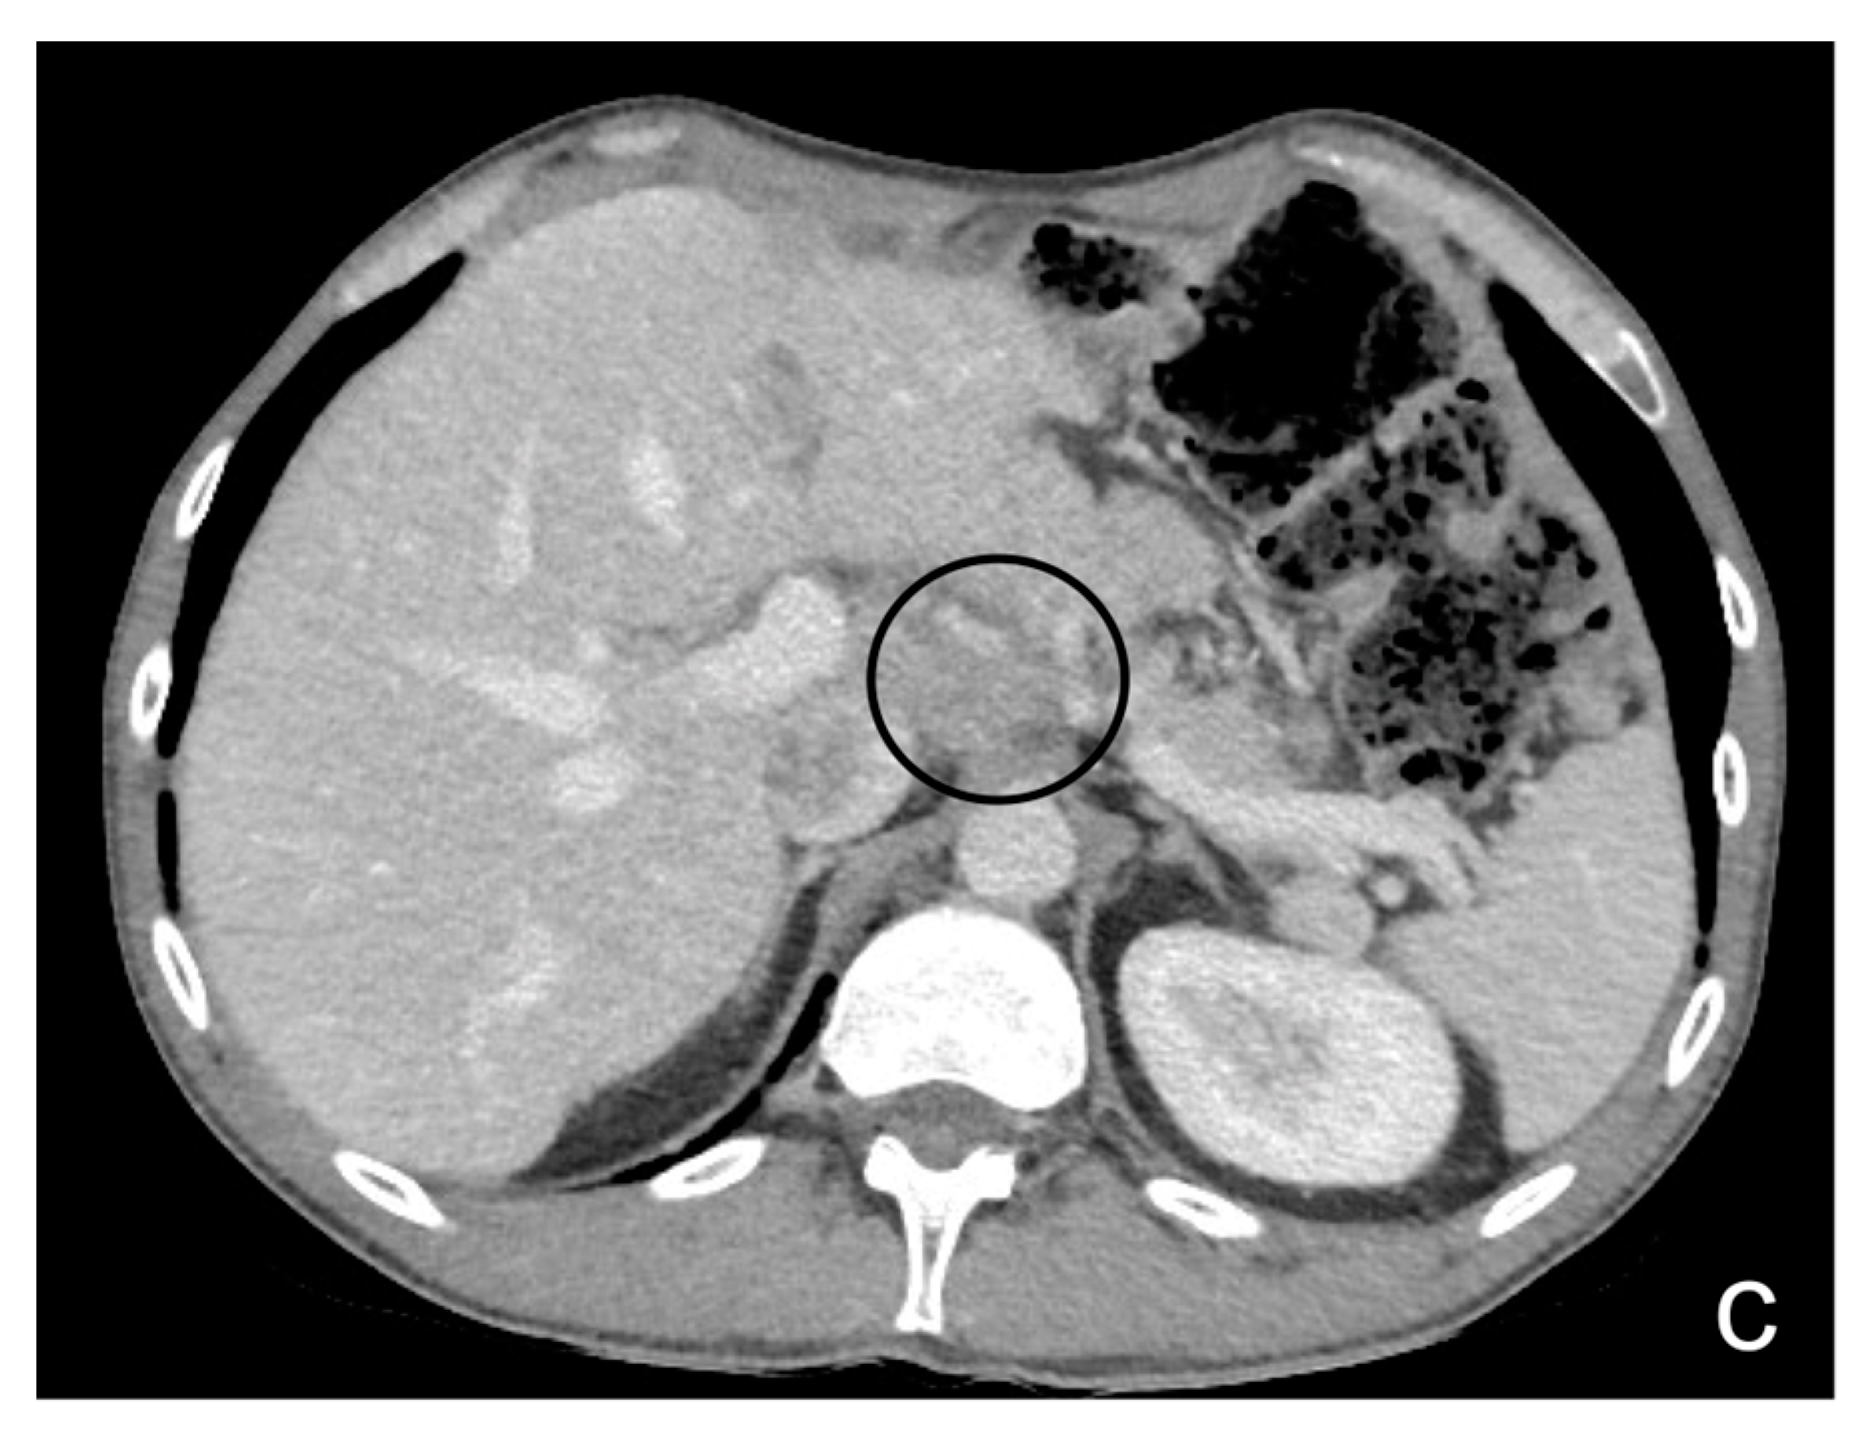

- Nodular pattern: characterized by the presence of nodular implants >5 mm in diameter (Figure 8).

- Plaque pattern: confluent nodular tumor implants that are typically located on the lower surface of the right diaphragm and may manifest as a depression of the liver surface, mimicking capsular or subcapsular liver metastases. They present as areas of low attenuation relative to the parenchyma on postcontrast scans [94,95] (Figure 10).